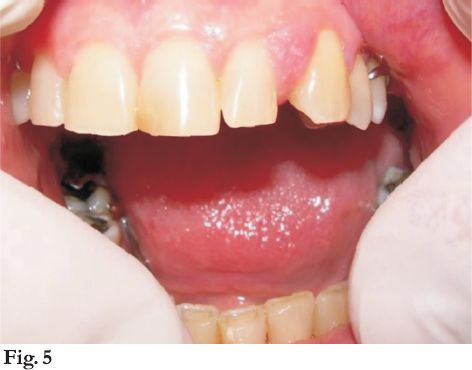

Al examen clínico se constató una tumefacción que por vestibular abarcaba la papila interdentaria entre las piezas 2.2 y 2.3, y por palatino se extendía 1,5 cm hacia distal y en sentido lateral desde mesial del 2.2 a distal del 2.3.

Cubierta de mucosa normal, firme , indolora y no sangrante. Concomitantemente se observa diastema de unos 3 milímetros entre las piezas mencionadas (fig. 5 y 6).